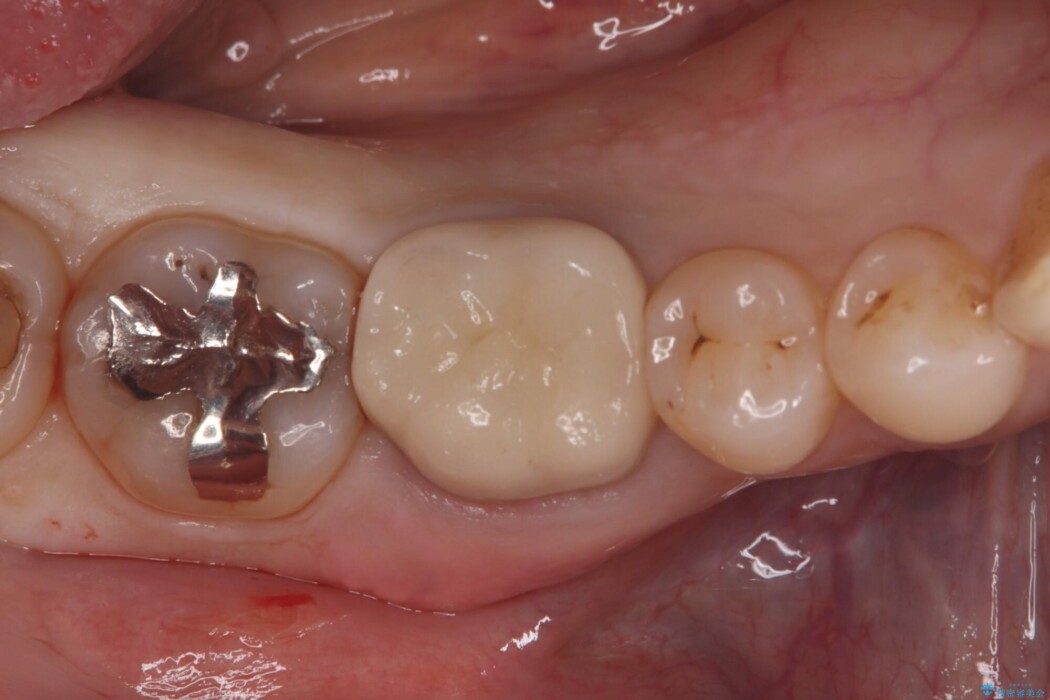

診査の結果、古い銀歯の隙間から新しい虫歯が広がっていました。ここは噛む力が強くかかる場所のため、このまま詰め物で治すと、部分的な詰め物では残存している自分の歯に負担が集中し、将来的に歯が割れてしまう「歯冠破折」のリスクが高い状態でした。

虫歯を丁寧に除去し、審美性・耐久性に優れたセラミッククラウンにやり替える治療計画を立案しました。